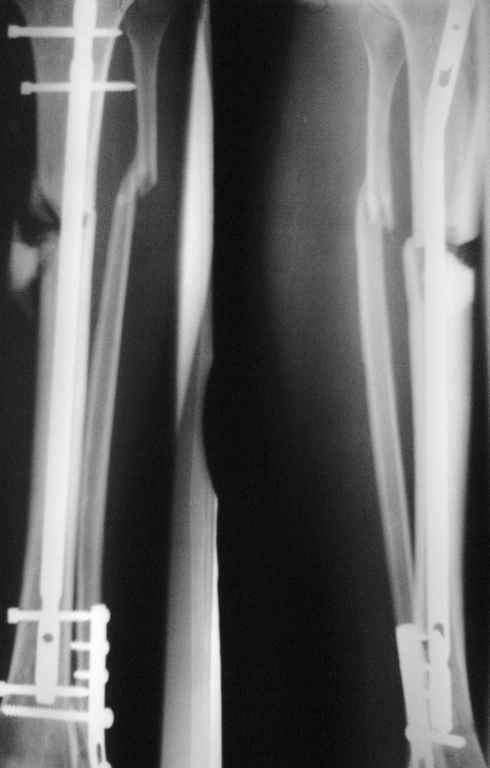

Пролежень+несращение

Б-й О.25лет прооперирован 7 мес. назад, сформировался пролежень ок. 2-х мес назад.Передвигается с 50% нагрузкой с помощью трости.

Предлагается остеотомия м/берцовой кости,удаление фрагмента, динамизация стержня с введением поллерного винта.

Надо полагать, пролежень вызван отломком по медиальной поверхности - конечно, его давно надо удалить. Здесь можно убрать самый дистальный винт, второй там динамический. Пора бы уже и убрать позиционный винт из синдесмоза. Насчет остеотомии малоберцовой кости - можно сначала пару месяцев подождать результатов динамизации. Куда намереваетесь ввести отклоняющий винт и зачем?